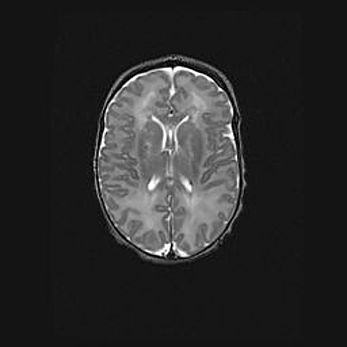

Церебральная ишемия II.

Возраст: 5 дней

Вес: 3400 г

Пол: женский

Окружность головы: 35 см

Срок гестации: 39 недель

Церебральная ишемия – это заболевание, характеризующееся недостаточностью (гипоксией) либо полным прекращением (аноксией) снабжения мозга кислородом по причине закупорки одного или нескольких сосудов. Это приводит к  что метаболическим расстройствам различной степени тяжести в тканях головного мозга, развитию коагуляционных некрозов и гибели нейронов.